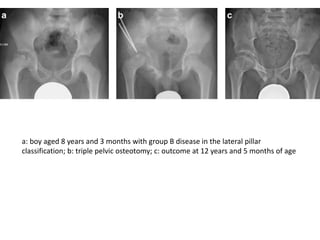

a: boy aged 8 years and 3 months with group B disease in the lateral pillar

classification; b: triple pelvic osteotomy; c: outcome at 12 years and 5 months of age

a: boy aged8 years and 3 months with group B disease in the lateral pillar classification; b: triple pelvic osteotomy; c: outcome at 12 years and 5 months of age